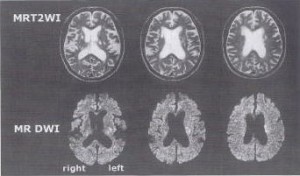

まず、脳神経外科医に最終MRI検査と読影をして頂いた。そこで前頭葉の損傷に注目、家族の観察と受傷部位を結ぶべく、必要な検査を検討した。